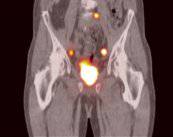

La Hiperplasia Prostática Benigna (HPB) es una condición común en hombres mayores de 40 años, caracterizada por el crecimiento no canceroso de la próstata. Este agrandamiento puede obstruir parcial o totalmente el flujo de orina, provocando molestias urinarias que afectan la calidad de vida del paciente.